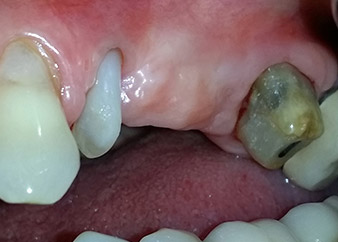

A 58-year-old female patient complained of pain and increased mobility of her bridge abutment tooth 24. Periodontal inflammation was present with pocket depths of 7 mm mesiobuccally and more than 12 mm distally, as well as third-degree furcation involvement. Moreover, the radiograph revealed an extensive periodontal lesion around the apical region of the (alio loco) endodontically pretreated tooth 24 (Fig. 1).

One year earlier, teeth 25 and 26 had been extracted due to trauma and for endo-perio reasons, prior to the placement of the bridge. A combined endo-perio lesion was diagnosed for tooth 24, of unclear aetiology. The patient wanted to keep her bridge abutment teeth 24 and 27 and would not accept a final, or even temporary, removable prosthesis. Therefore, it was agreed to make all efforts to retain both teeth, in spite of their poor prognosis as based on radiological and clinical findings.

One month later, on the day of surgery, pain and inflammation at tooth 24 were minimal, but mobility of Miller class 2 was still present. After opening the flaps and cleaning the periapical and peri radicular infected tissue, the extent of the bone defect became obvious (Figs. 2 and 3).

At the buccal root, all vestibular and distal bone was missing. Attachment was essentially restricted to the palatal root, underlining the preliminary poor prognosis. Tooth 27 also showed a reduced horizontal attachment and a minimal apical rarefaction (cf. Fig. 1) without clinical symptoms.

total loss of bone and attachment

Fig. 2 and 3: After raising flaps, one month after endodontic revision and initiation of full-mouth periodontal therapy, the buccal root of tooth 24 showed a total loss of bone and attachment.